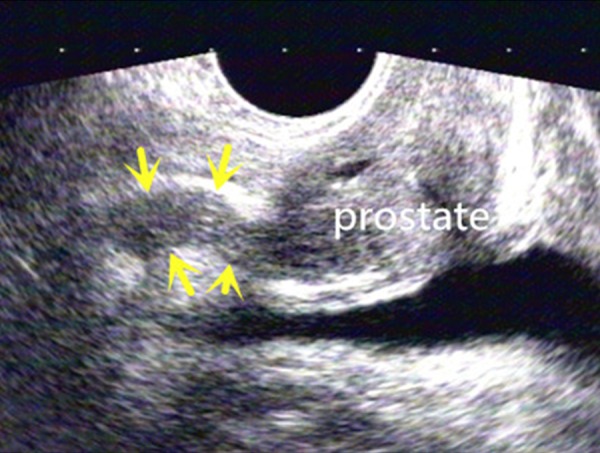

Figure 4.

TRUS scan above the prostate shows a hypoplastic SV as a thin and short structure with hypoechoic appearance (arrows).